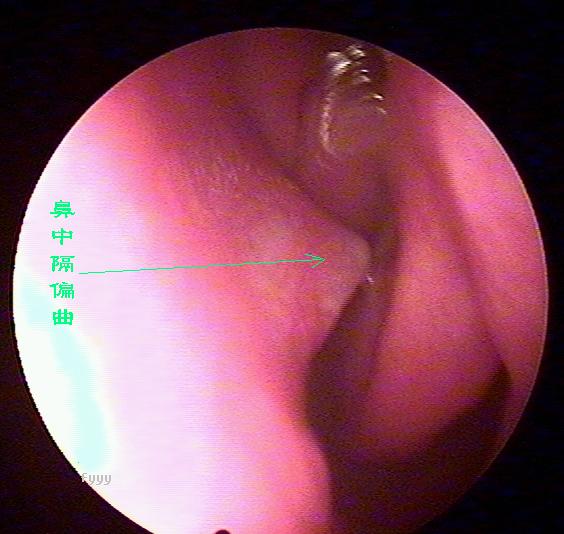

老流鼻血可能是鼻中隔偏曲惹的祸,鼻中隔偏曲部位经常会出现血管畸形,而且这里的粘膜也相对较薄,受气流、尘埃等刺激后容易破损、出血,主要症状为:交替性或持续性鼻塞,头痛,鼻出血及流脓涕等。且难以痊愈,经常发作。西安新城中大耳鼻喉医院耳鼻喉科推出的,快速无痛治疗鼻中隔偏曲。

2、鼻出血:鼻出血是鼻中隔偏曲较为常见的症状之一。发生在偏曲之凸面、骨棘或骨嵴的先进部,此处粘膜薄。常受气流和尘埃刺激易发生糜烂而出血。老是在洗脸的时候流鼻血是什么原因 ?

鼻中隔偏曲的诊断检查

鼻中隔偏曲进行鼻内检查以判断鼻中隔偏曲的类型和程度,注意鉴别鼻中隔粘膜肥厚和是否同时存在鼻内其它疾病,如原发病变—肿瘤、异物或继发病变—鼻窦炎、息肉等。 另一罕见者为鼻中隔梅毒瘤,其质地中亦较硬,但该处粘膜明显充血。

“ 狼牌内窥镜”可通过耳鼻咽喉等部位狭小通道直接看到常规仪器检查所不能看到的病灶,并可放大数十倍甚至百倍,有助于清晰而详细地观察到周围的病变,只需要5分钟即可检测出疾病病因,辅助医师进行精准治疗,告别耳鼻咽喉疾病治疗误区,具有不易漏诊而精准治疗的优点,被业界称为耳鼻喉科医生的“只眼睛”。